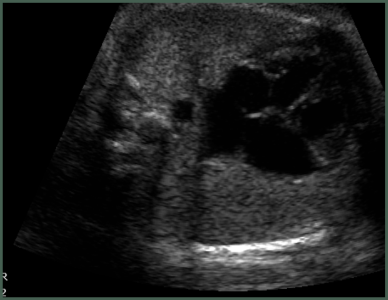

- Thorough scanning of your baby is done to know if baby is developing normally or not. Special attention is paid to brain, face, spine, heart, stomach, bowel, kidneys & limbs.